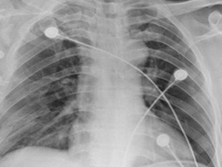

检查项目:

X线平片